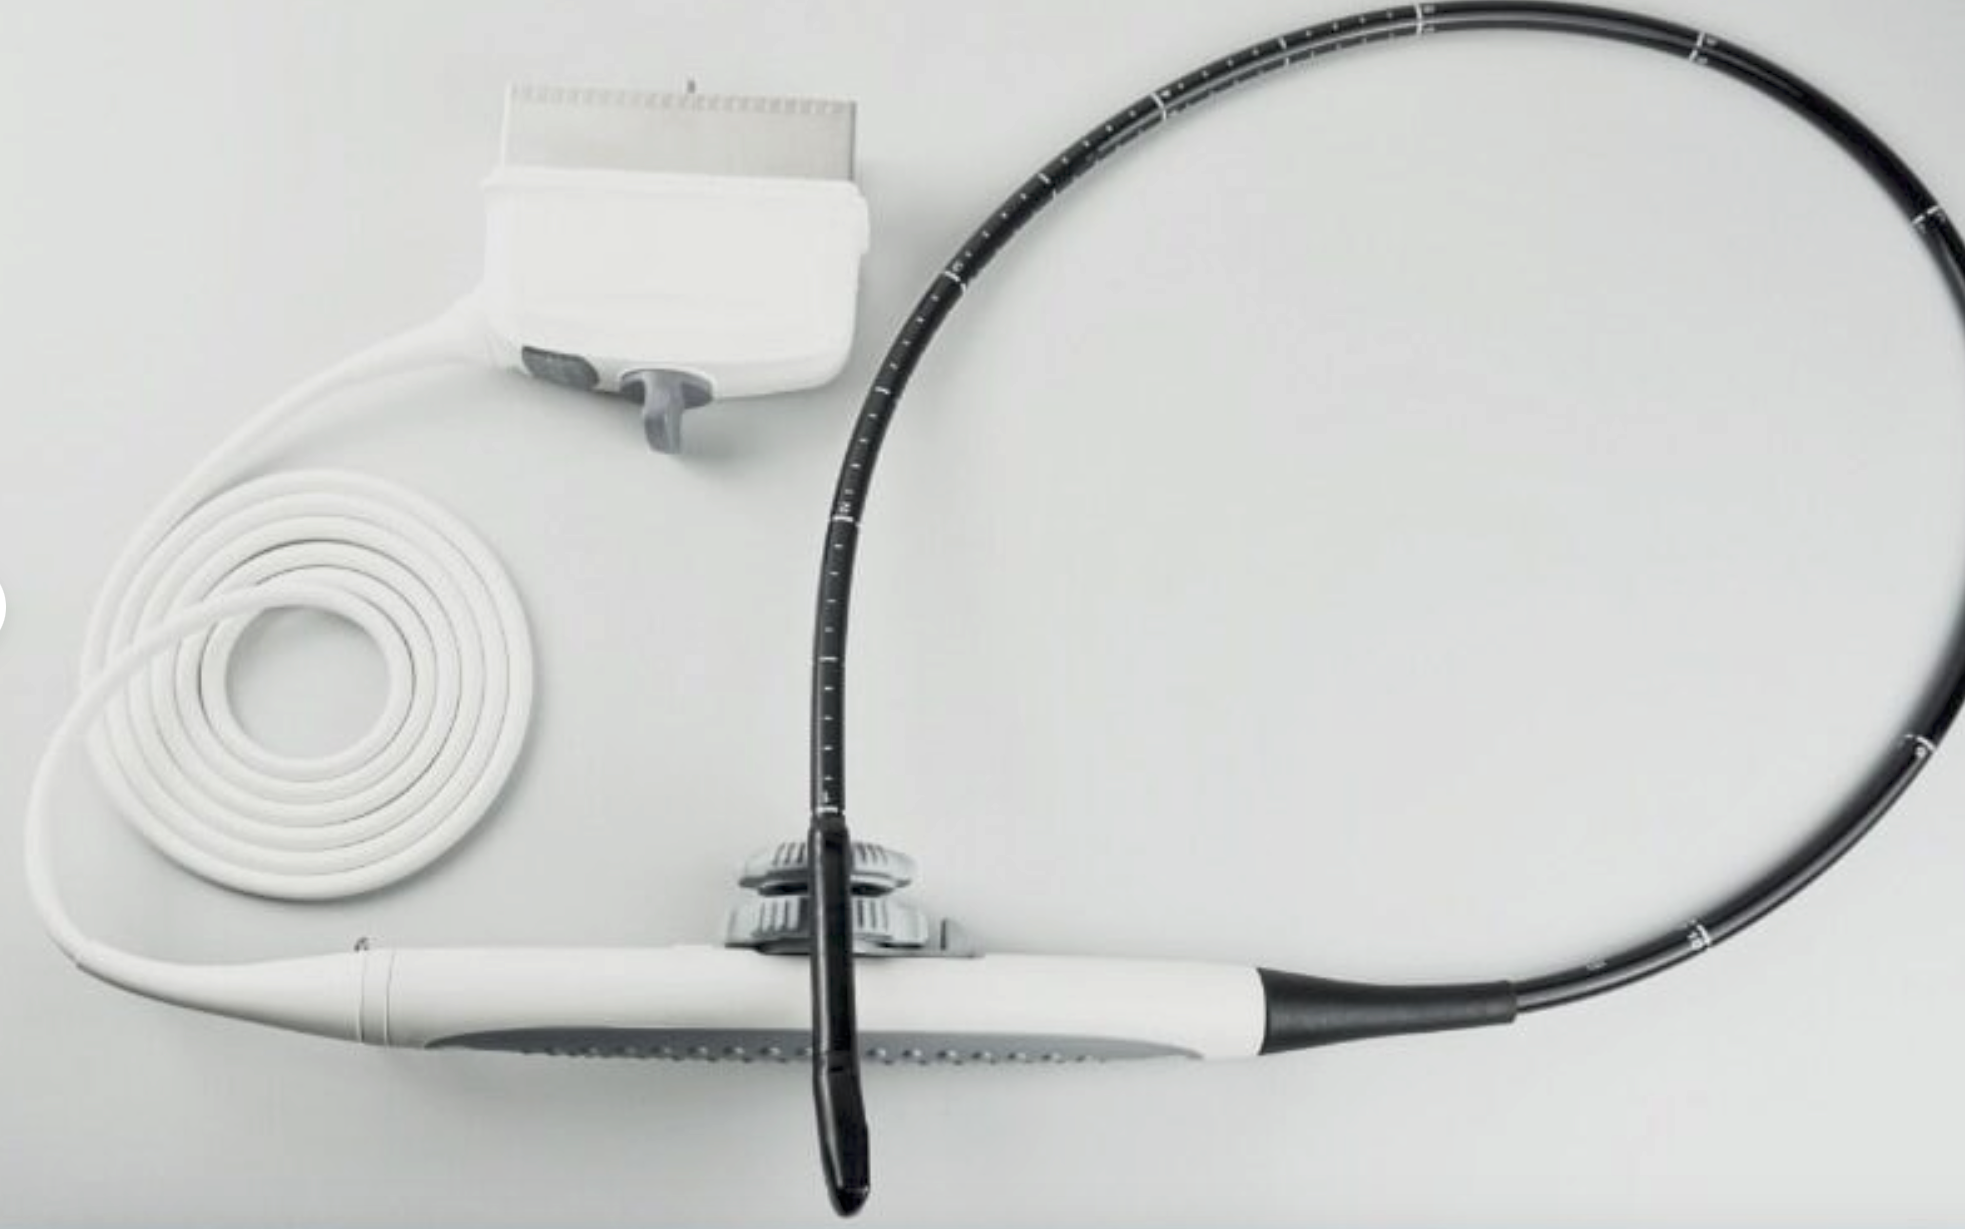

standard Probe: convex transvaginal 2 probes

Option probe: linear / Rectal probe

The portable ultrasound scanner is an essential tool for various medical environments. It offers the flexibility to conduct scans in clinics, hospitals, and even at home. Doctors and healthcare professionals appreciate its compact design, which facilitates ease of transport. Furthermore, the inclusion of both convex and transvaginal probes expands its usability, allowing practitioners to perform different types of examinations efficiently.